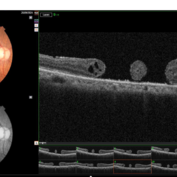

Fundus photograph of a 62 year old gentleman presenting with double adjacent full thickness macular holes in the right eye maintaining a vision of CF 3 mts.

OCT image of a 62 year old man after a blunt trauma by a tennis ball with a vision of CF 3 mt in the right eye.